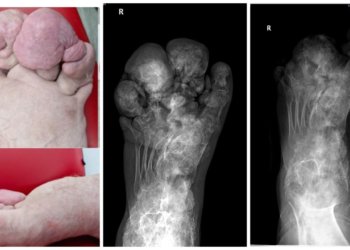

Новосибирские врачи из ННИИТО им. Я.Л. Цивьяна провели уникальную операцию 21-летнему жителю Братска Андрею Кочерыгину, страдающему редчайшим генетическим заболеванием –...